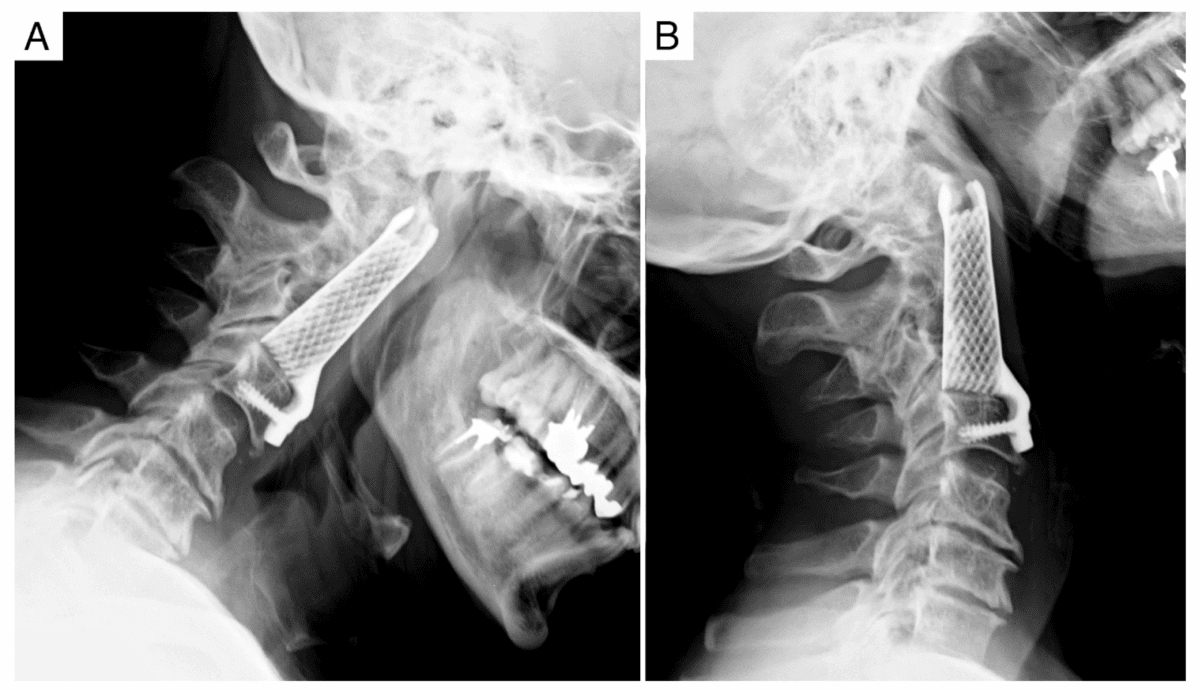

این جراحی به سرپرستی دکتر جوزف اوسوریو، دانشیار جراحی مغز و اعصاب در دانشکده پزشکی دانشگاه کالیفرنیا سندیگو در ژوئن ۲۰۲۵ انجام شد. تیم جراحی با بهرهگیری از تصویربرداری پیشرفته، هوش مصنوعی (AI) و چاپ سهبعدی توانستند ایمپلنتی دقیقاً متناسب با آناتومی بیمار طراحی و تولید کنند.

برخلاف ایمپلنتهای سنتی که همگی یک اندازه و یک شکل تولید میشوند، این دستگاه با استفاده از تیتانیوم پزشکی ساخته شد و به طور اختصاصی با ابعاد ستون فقرات بیمار تطابق پیدا کرد.

پزشکان قبل از جراحی، اسکنهای دقیقی از ستون فقرات بیمار تهیه کردند و با کمک هوش مصنوعی، طراحی ایمپلنت را انجام دادند. سپس قطعه نهایی با چاپ سهبعدی ساخته شد و در عمل جراحی به کار رفت.

این نوآوری باعث شد که ستون فقرات بیمار با دقت بیشتری تنظیم شود، پایداری بیشتری داشته باشد و بهتر حمایت شود. این روش جدید میتواند درمان بیماریهایی مانند: تنگی کانال نخاعی، فرسایش دیسکها و انحراف ستون فقرات را به طور چشمگیری بهبود دهد.